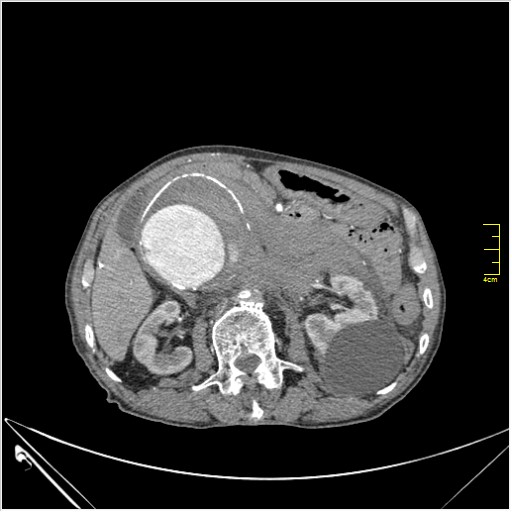

КТ брюшной полости. Мужчина с пальпируемой опухолью в животе

Пациент Т. 64 года, обратился на КТ брюшной полости амбулаторно (!), по направлению семейного врача с диагнозом abdominal mass, буквально: образование брюшной полости.

Uzgraph писал(а):Случай интересный - ногу сломишь. Вроде бы анефризма брюшной аорты(особенно по УЗИ), но что тогда за образования сидят на левой почке - онкология?

ИМХО простые кисты.